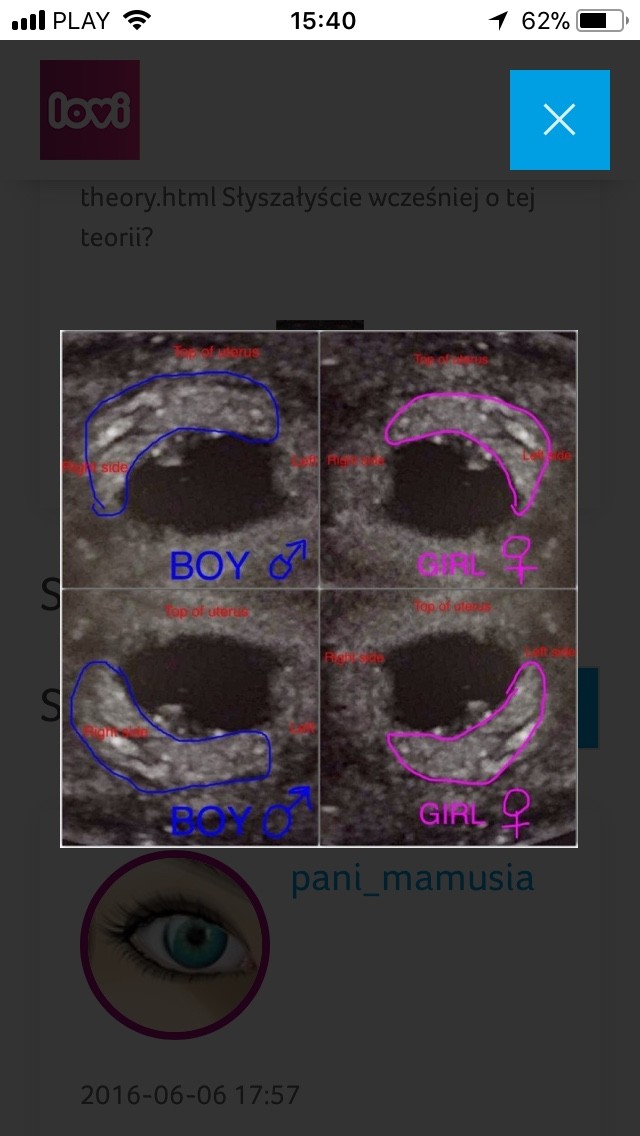

A słyszałeście o metodzie ramzi określania płci na podstawie zdjęć usg z 6-8tc? :D dla niektórych kolejna bujda ale mi daje kolejną nadzieję że tym razem dziolche ustrzelilismy [emoji12]

Potem na podstawie zdjęć z okolic 12 tc i położenia wyrostka niby niemal 100% można określić.

Teraz to juz nam metlik w glowie :) czy to zdjecie to lustrzane odbicie czy faktyczny obraz? Na moim usg wychodzi, ze dzidzia jest z lewej strony, ale przyjelam, ze to lustrzane odbicie czyli w rzeczywistosci jest z prawej.